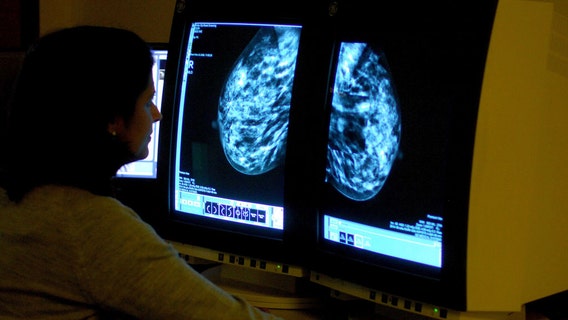

Artificial intelligence model to help scientists predict whether breast cancer will spread

Oncologists in the U.K. have developed an AI model to help predict whether aggressive forms of breast cancer will spread based on changes in a patient’s lymph nodes.

Regular mammograms for women should start at 40, not 50, US health panel recommends

A federal task force is recommending that women start getting every-other-year mammograms at age 40 instead of waiting until 50.